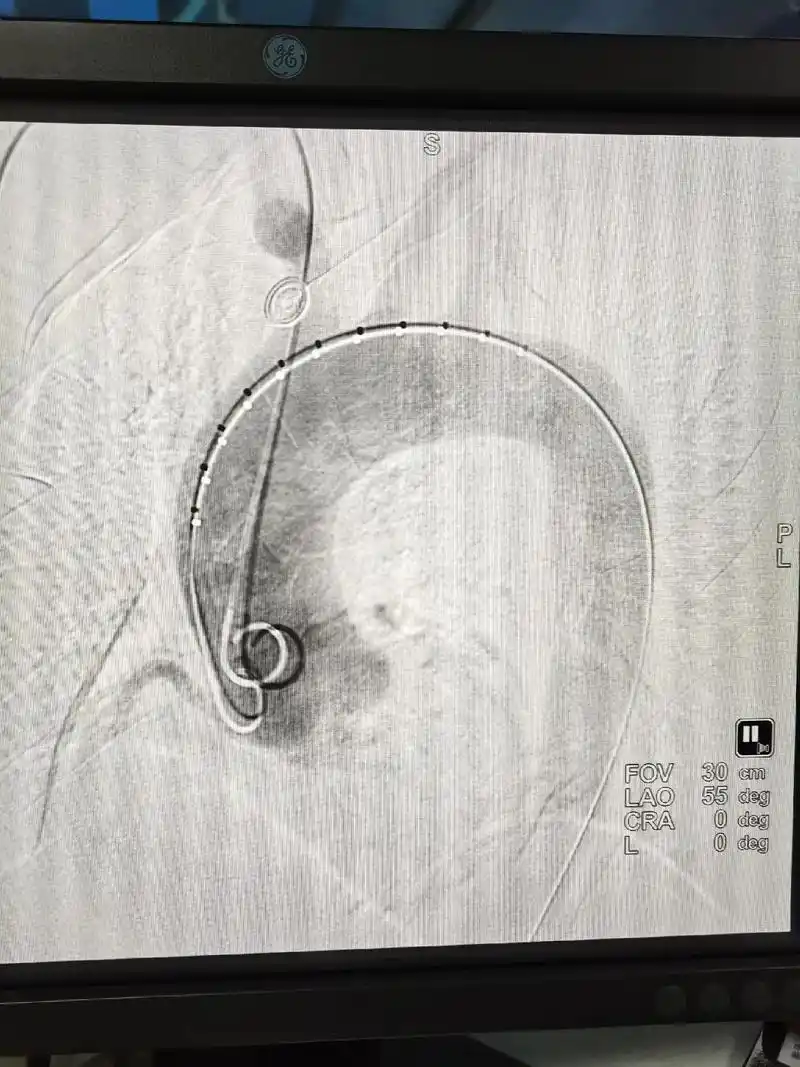

分享近日一例主动脉夹层—壁间血肿(术后已康复出院 - 抖音